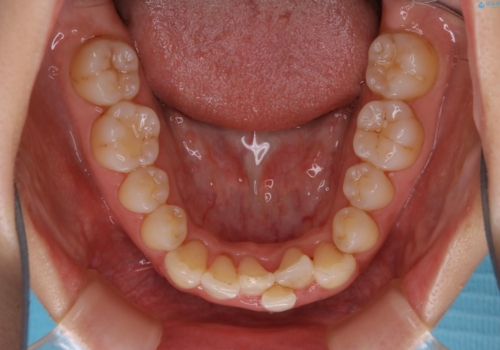

前歯のがたつきを無くすためには、スペースを確保する必要があります。上の前歯のがたつきは軽度ながたつきのため、歯と歯の間を研磨をして、そのスペースを使い並べていきます。下の前歯は、1本前歯を抜いて研磨せずに、その抜歯したスペースを使い並べることになりました。

下の前歯は、スリーインサイザー仕上げと言って、通常前歯は4本ありますが(犬歯はいれていない)、そのどれか1本を抜歯して前歯を3本にして矯正治療を行うことを言います。また、先天的に歯の本数が少ない方もいますので、矯正治療を行っていなくても元々スリーインサイザーの方もいます。